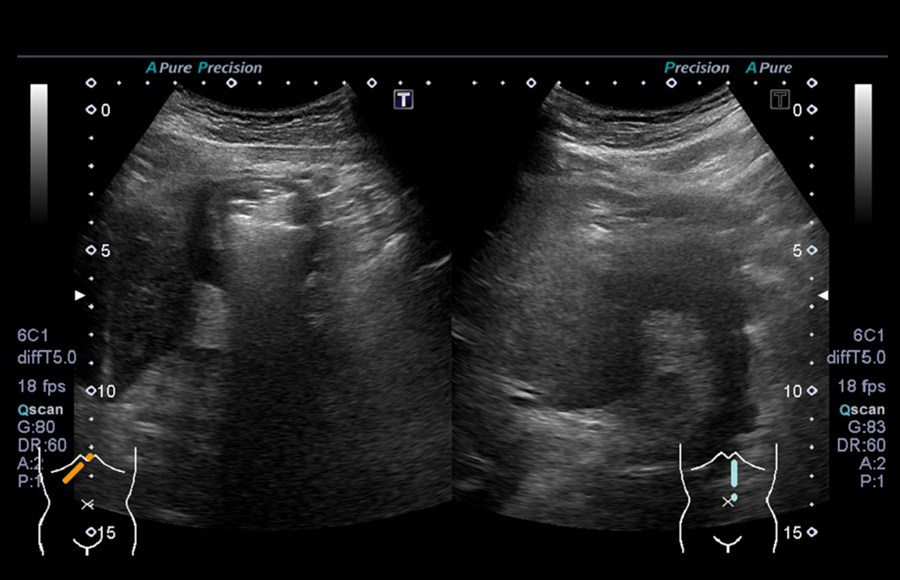

超音波(エコー) 診断画像

- 転移性肝がん

- 胆嚢ポリープ

- 胆石

- 大腸がん

- 前立腺肥大・前立腺がん

- 腎細胞がん